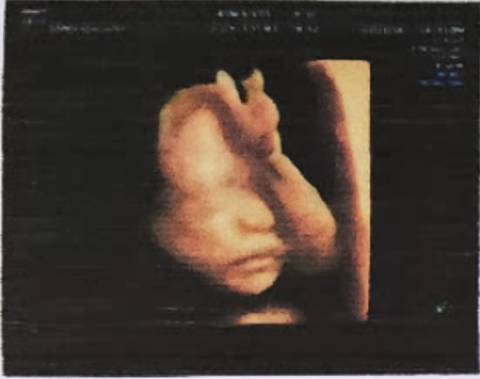

女儿特别调皮,每天都会在肚子里大闹天宫。每次产检医生都会说她一直在动,没停过。在肚子里就这么爱动,出生了还了得。